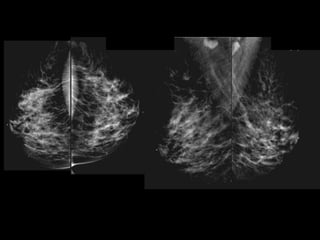

HISTORY

โ€ข 65 yo female

โ€ข Presents from OSH with worsening โ€žleft

breast swellingโ€Ÿ for 8-9 months

โ€ข New 1 month history of โ€žchange in left

nippleโ€Ÿ

Current Bilateral Mammogram

RCC      LCC             RMLO       LMLO